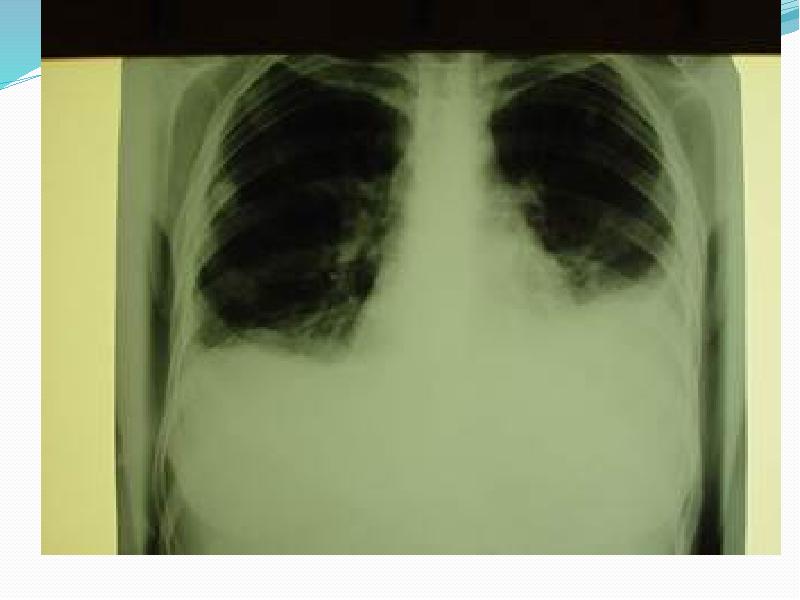

- 17. Асқынулары Ерте Пневмоторакс (үдемелі, клапанды) Гемоторакс Жүрек тампонадасы Респираторлы дистесс-синдромы Хилоторакс

- 23. Инструментальды тексеру әдісі Рентгенологиялық тексеру (рентгенография, рентгеноскопия) Компьютерлік томография УДЗ